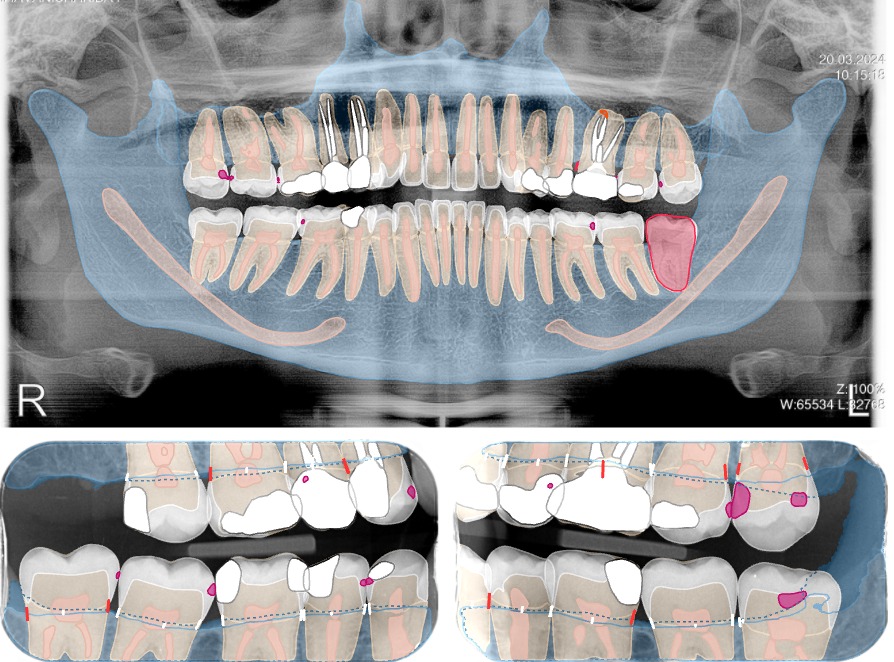

2️⃣ AI Diagnocat provede analýzu

Systém automaticky označí potenciální kazy, záněty, parodontální problémy a další rizika.

Na obrázku můžete vidět zobrazení všech drobných kazů ke sledování, 3 větší kazy na osmičkách vlevo nahoře i dole, které by bylo dobré ošetřit a dále můžete vidět nepříznivé postavení osmičky vlevo dole, která je pravděpodobně určena k extrakci.